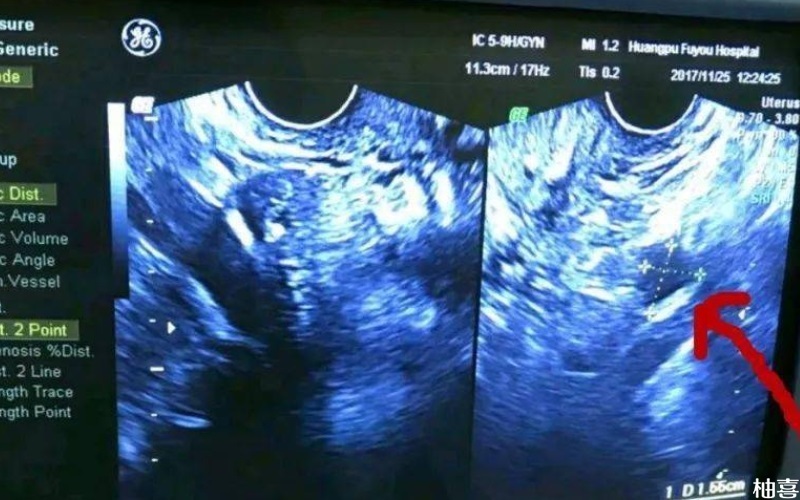

不仅如此,子宫内膜环境对胚胎着床至关重要。良好的子宫内膜环境有利于胚胎的发育,从而提高成功率,而子宫内膜薄、子宫内膜息肉、粘膜下子宫肌瘤、宫腔粘连及子宫纵膈等,都会影响子宫内膜容受性,从而影响胚胎着床。因此具体是否能怀孕成功,建议各位不孕不育症夫妇以自身实际情况为准。